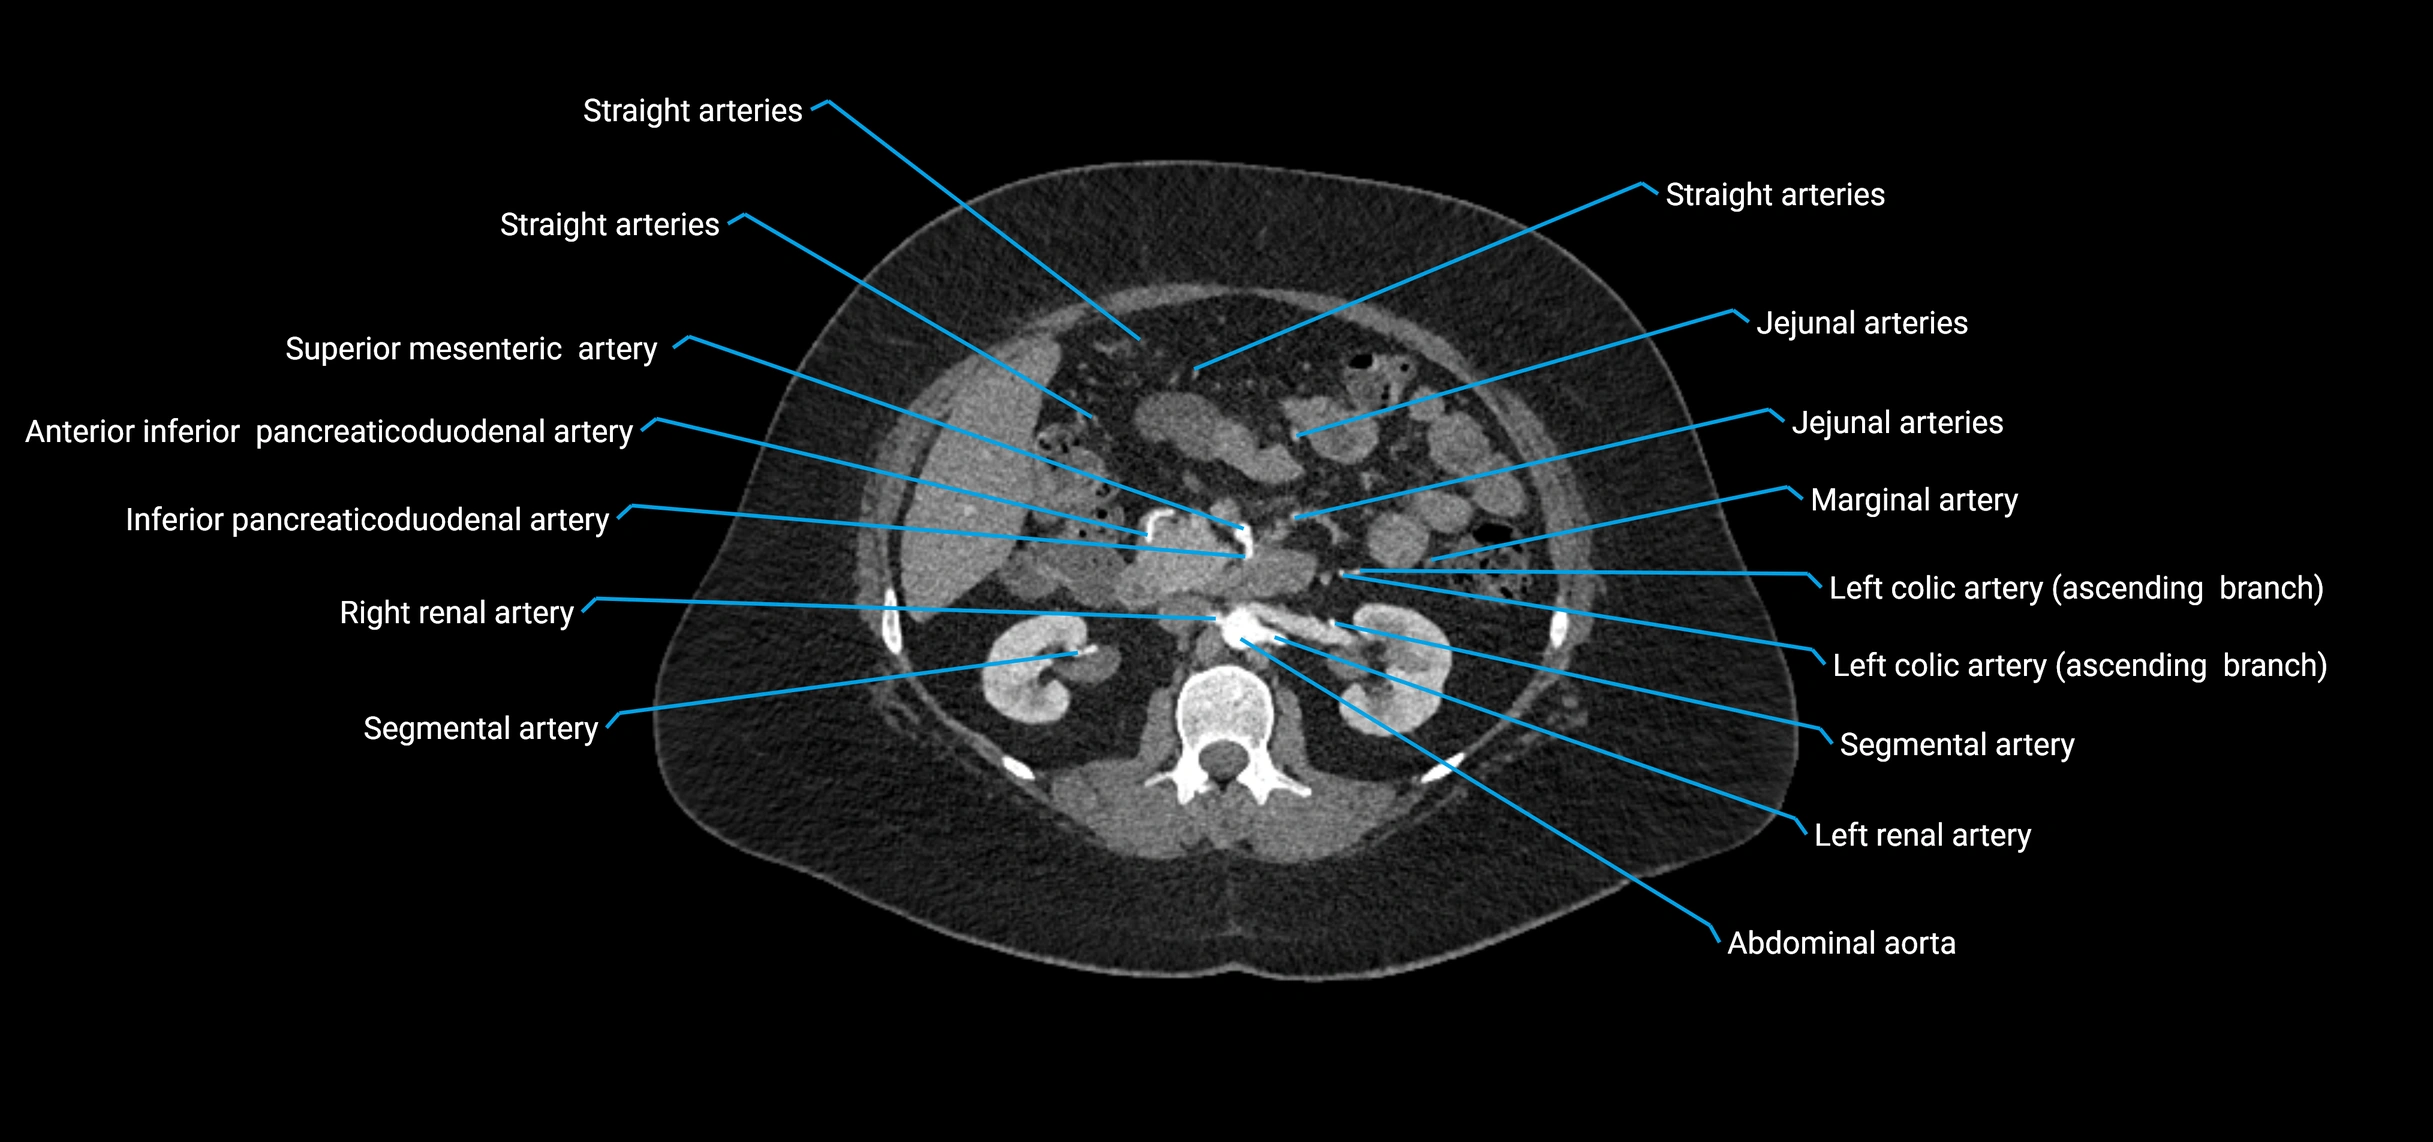

CT images

image

Contrast-enhanced CT (CTA):

• Gold standard for abdominal aortic imaging

• Provides excellent detail of lumen, wall, aneurysm, thrombus, and branch vessels

• Multiplanar and 3D reconstructions help in aneurysm measurement, stent graft planning, and dissection evaluation